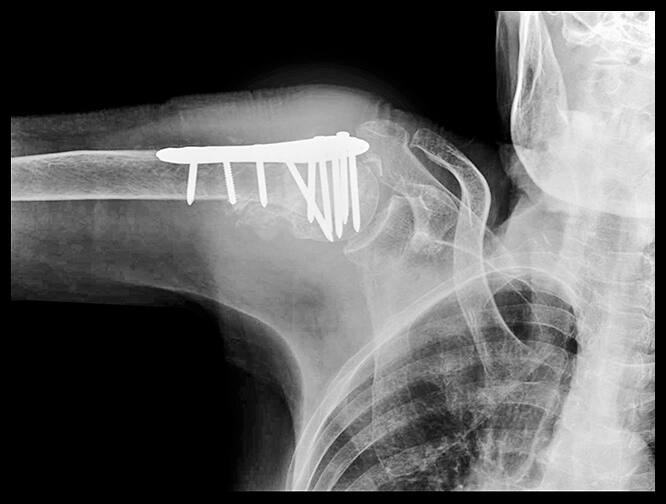

Je nach Leidensdruck durch Schmerzen und Bewegungseinschränkung muss individuell entschieden werden, ob eine Operation zum Einsetzen einer Endoprothese des Schultergelenks infrage kommt. Zu lange sollte man die Entscheidung nicht herauszögern, denn wenn sich Sehnen und Muskeln der Schulter versteifen und zurückbilden, kann das künstliche Gelenk die Beweglichkeit nicht mehr zurückbringen. Künstliche Schultergelenke sind wesentlich seltener im Vergleich zu Hüft- oder Kniegelenken. In Deutschland werden jährlich etwa 25.000 Implantationen von Schultergelenksendoprothesen durchgeführt.

Künstliches Schultergelenk bei einer Arthrose des Schultergelenks

Neben Teilprothesen des Schultergelenks werden Schulter-Totalendoprothesen (TEP) eingesetzt, dabei wird das Schultergelenk vollständig ersetzt. Nach durchschnittlich 3 Monaten ist wieder eine alltagstaugliche Beweglichkeit erreicht. In 90% der Fälle (abhängig von der Beweglichkeit vor der Implantation) sind Überkopfarbeiten wieder schmerzfrei sowie Tragen und Heben von Lasten bis ca. 5 kg möglich. Sport ist je nach Grad der Vorschädigung ebenfalls möglich, wobei riskante Sportarten mit Sturzgefahr vermieden werden sollten.